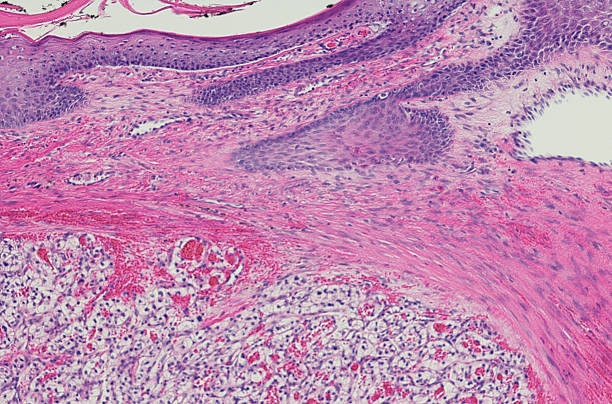

신장암 초기증상 진단 방법

신장암은 혈액 검사나 소변 검사로는 조기 진단하기 어렵습니다. 따라서 건강을 유지하고자 하는 목적으로는 초음파 검사를 적어도 일 년에 한 번 받는 것이 좋습니다. 초음파 검사를 통해 작은 크기의 신장암도 조기에 발견할 수 있습니다.